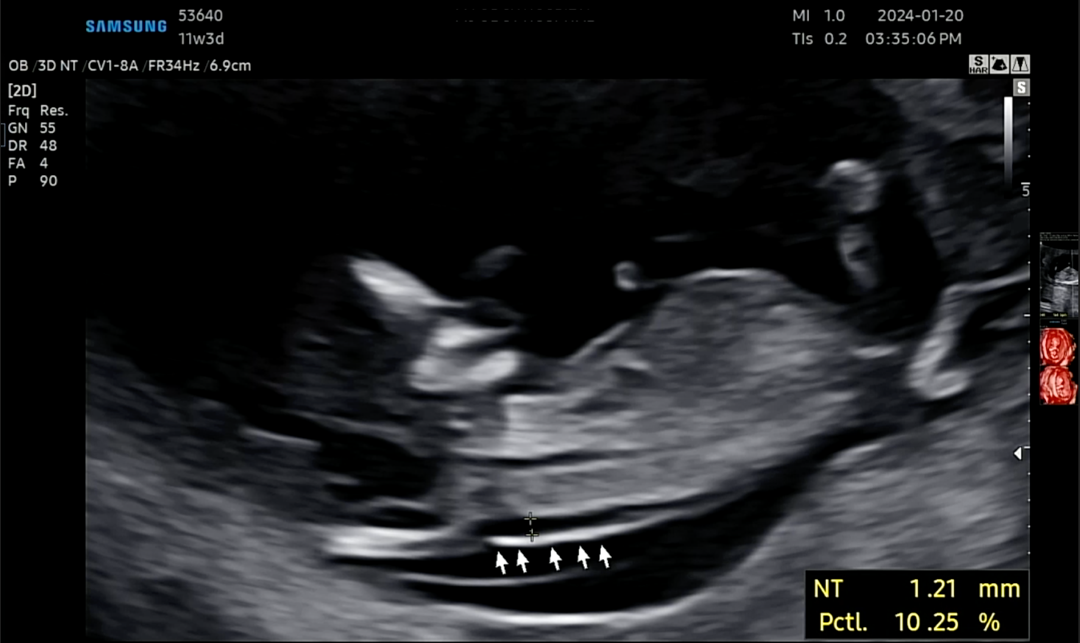

11주 3일 1차 정밀검사 받고왔어요

1차 정밀검사 받으면서 투명대검사 코뼈 보고 왔네요 의사 선생님은 다 정상 이라고 아가도 잘 움직이고 잘 보여줘서 금방 끝났는데 집에 와서 보니깐 측정 위치가 잘 못 된건가 싶기도하고 투명대 검사 목 덜미 두께 아닌가요? 어째 측정 위치가 엉덩이 쪽인거 같기도한데 혹시 아시는 분 계시나요?

왼쪽이 머리 아닌가요? 맞는 거 같아요!

왼쪽이 머리라서 맞게 측정된 것 같아요!